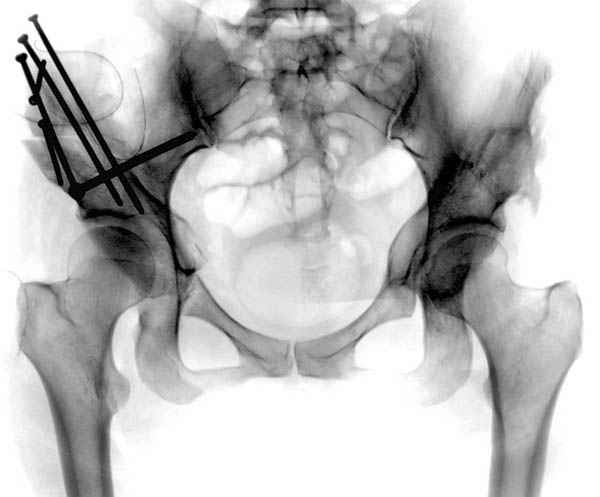

Как раз к обсуждению. Обратилась за косультацией 21-летняя девушка с жалобами на боли в левом тазобедренном суставе. Что можно ей порекомендовать?

coxa.jpg